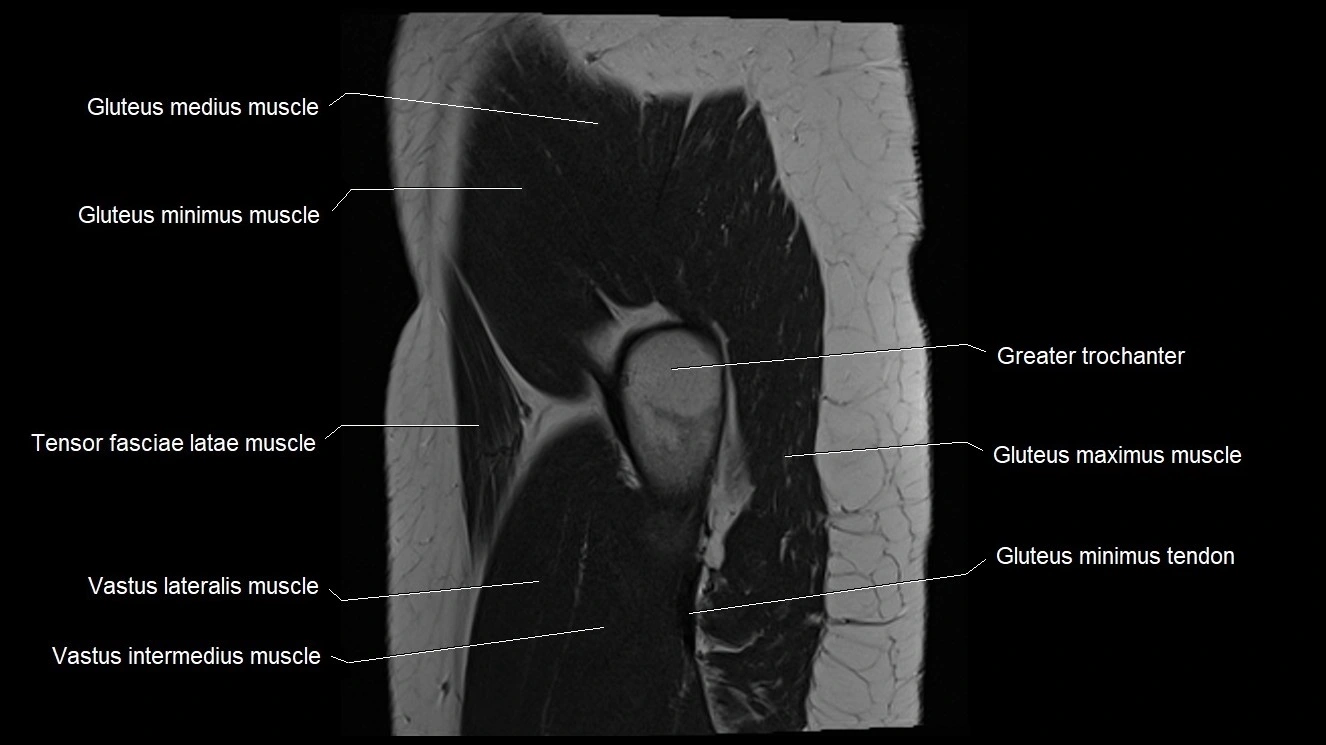

- Gluteus medius muscle

- Gluteus minimus muscle

- Gluteus minimus tendon

- Greater trochanter

- Tensor fasciae latae muscle

- Vastus intermedius muscle

- Vastus lateralis muscle